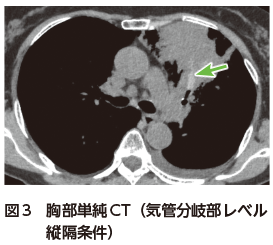

胸部単純X線写真では左上中肺野縦隔側に広範な浸潤影を認める(図1).胸部CTでは左上葉に,中枢から拡がる浸潤影を認め,周囲にすりガラス影を伴う(図2).胸部CT縦隔条件では,中枢気管支内に粘液栓を認め,内部のCT値が上昇している図3).いわゆる高吸収粘液栓(high attenuation mucus:HAM)の所見である.

ABPMは気道内に定着した真菌によって発症する慢性炎症性気道疾患であり,Ⅰ型・Ⅲ型アレルギー反応が関与している.真菌感染症とは異なり真菌の組織浸潤は認められず,菌体は気管支内粘液栓に限局している1)Aspergillus fumigatusが原因として最も多く,アスペルギルスが原因の場合にはABPAと呼ばれる.ABPMの特徴的な画像所見として,気管支内を充填する粘液栓・中枢性気管支拡張がある.約25%の症例では,真菌が酸化物として産生する鉄やマンガン,カルシウムが高吸収域(CT値で70 HU以上)として認識され,HAMとなる2)好酸球性肺炎を合併した例では,粘液栓の末梢に浸潤影やすりガラス影を認める2)